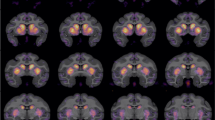

Effects of global serotonin (5-HT) depletion: (a) 5-HT-depleted animals showed an enhanced tendency to shift after being rewarded (ie, decreased win-stay). (b) Lesioned animals showed a faster increase in lose-shift behavior compared with control animals, but the effect disappeared over sessions. (c) Lesioned rats completed fewer reversals than sham-operated rats. A significant effect of session indicates that both groups improved their performance over time.

The total number of reversals achieved by the animals (Figure 4c) increased over sessions (F(4, 52)=4.251, p<0.01), but no interaction was found with the variable group (F(4, 52)=1.372, NS). There was a significant effect of group in the number of reversals completed (F(1, 14)=15.774, p<0.001), with lesioned animals completing fewer reversals (p<0.001). Depleted animals were also faster to respond to the illuminated apertures (F(1, 14)=13.267, p<0.001), but no difference was found in the latency to collect the reward from the food magazine, in the total amount of food pellets earned, and in the number of ‘incorrect’ choices.